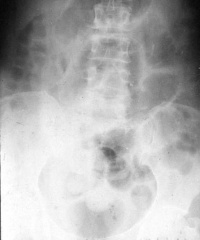

小肠梗阻

X线站立位时见小肠“阶梯样” 液平。平卧位时见积气肠管进入盆腔

小肠梗阻X线